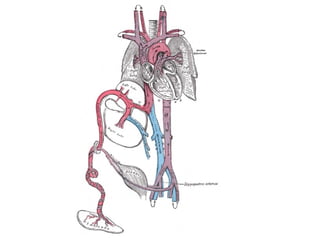

Pulmonary sling (1/2) Linker a pulm komt uit de rechter en verloopt tussen oesophagus en trachea en comprimeert rechter hoofdbronchus. Karakteristieke compressie: achterzijde trachea, voorzijde oesophagus. Radiologyassistant.nl

Pulmonary sling (2/2) Anomalie van Li a.pulm Karakteristieke compressie: achterzijde trachea, voorzijde oesophagus  Asymmetrische longinflatie tnv Re Geassocieerd met congenitale hartzkt, complete trachearingen,anomalie Re bronchus Donnelly 16

Pulmonary sling (1/2)Linker a pulm komt uit de rechter en verloopt tussen oesophagus en trachea en comprimeert rechter hoofdbronchus. Karakteristieke compressie: achterzijde trachea, voorzijde oesophagus. Radiologyassistant.nl

Pulmonary sling (2/2)Anomalie van Li a.pulm Karakteristieke compressie: achterzijde trachea, voorzijde oesophagus Asymmetrische longinflatie tnv Re Geassocieerd met congenitale hartzkt, complete trachearingen,anomalie Re bronchus Donnelly 16